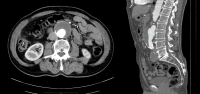

Ejemplo de película:

- AAA infrarrenal, diámetro 54,2 mm

- Aneurisma de la A. iliaca communis derecha, diámetro 41,1 mm